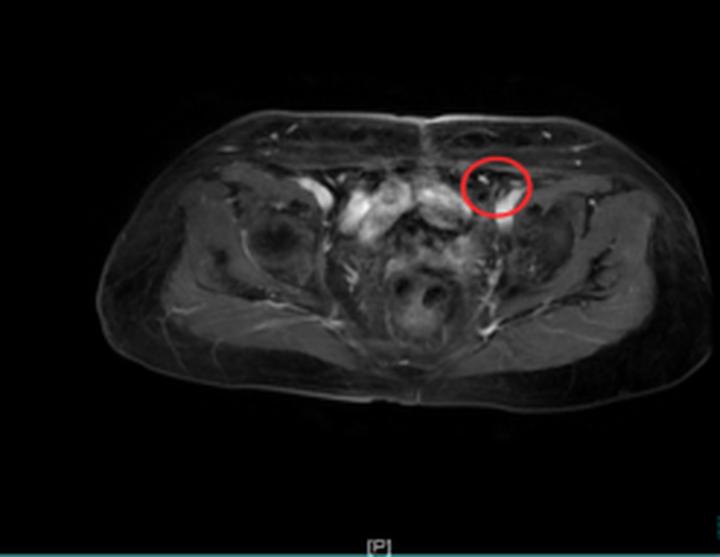

治疗过程顺利,相关指标逐步好转。用药2周期后,疗效评价即达到部分缓解(PR);用药6周期后,疗效评估进一步提升,达到完全缓解(CR)。更令人欣慰的是,整个治疗过程中患者耐受性良好,未出现严重血液学毒性及胃肠道反应,生活质量得到有效保障。目前,患者仍在维持用药中,持续受益于该治疗方案。

治疗前 治疗后